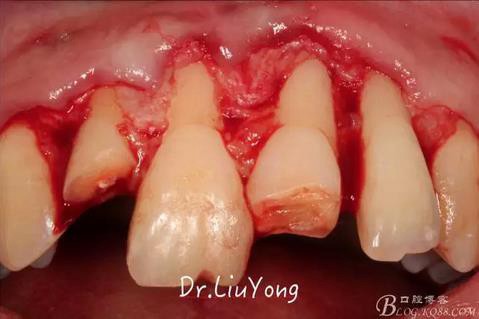

系帶手術(shù)后兩周,進(jìn)行上頜前牙唇側(cè)的牙齦退縮的手術(shù)治療,由于局部附著齦缺如及牙齦厚度不足,因此同期進(jìn)行上皮下結(jié)締組織移植,解決附著齦及牙齦厚度不足的問(wèn)題。

術(shù)中,可見明顯的唇側(cè)骨開裂,如上圖